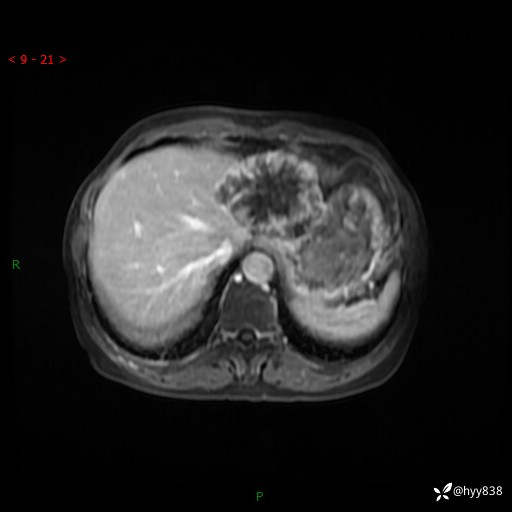

辅助检查:MRI

T2WIfs+DWI

增强(动脉期+静脉期+延迟期)